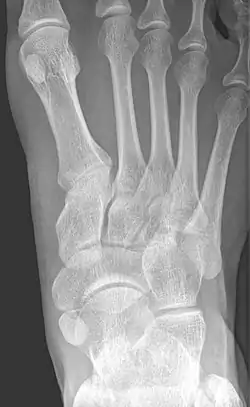

From left to right: Type 1, 2 and 3

Type 2